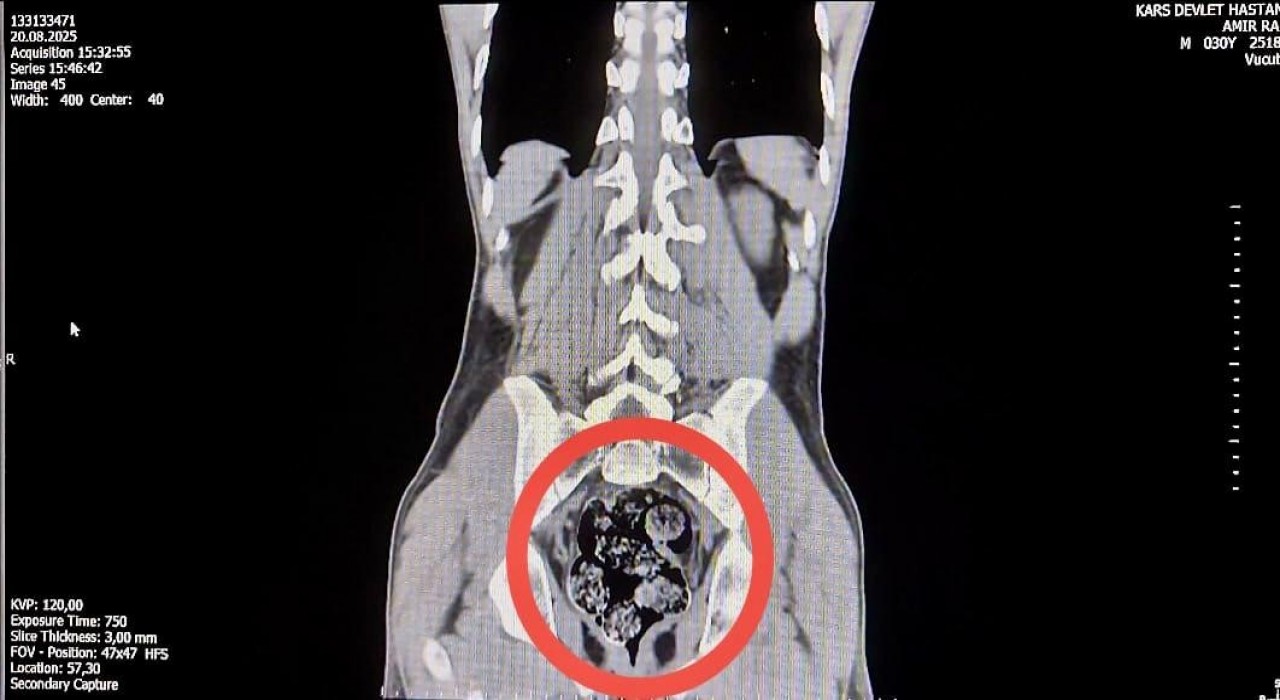

İl Emniyet Müdürlüğü’ne getirilen ve durumundan şüphelenilen kuryelerden Shekarbaghanı, detaylı arama için Kars Harakani Devlet Hastanesi’ne götürüldü. Hastanede yapılan emar ve röntgen kontrollerinde şüphelinin makatında cisim olduğu belirlendi. Yapılan cerrahi müdahalede, şüphelinin makatından 7 parça halinde 203,02 gram metamfetamin çıkarıldı.